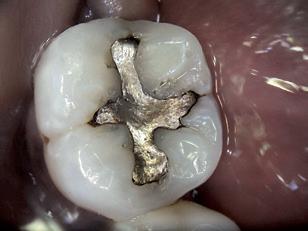

9. Patologisk tap av tannsubstans ved attrisjon/erosjon

Tilstanden må være grav for å være stønadsberettiget. Med grav patologisk attrisjon/erosjon menes tilstander som vil være av vesentlig betydning for funksjon og estetikk. Behandler skal i journalen dokumentere at medført skade har gitt vesentlig forringelse av tannhelsen. Før stønadsberettiget behandling påbegynnes, skal tilstandens alvorlighetsgrad og medførte skader dokumenteres.

Stønad gis også ved tilsvarende grav patologisk slitasje av kroner og/eller innlegg.

Behandlingen skal planlegges ut fra sykdomsaktivitet, langtidsprognose og være mest mulig vevsbesparende der behandling med plastisk materiale er førstevalg. Dersom kroneterapi anses nødvendig skal begrunnelse for valget journalføres. Det skal dokumenteres at kroneterapi vil føre til en vesentlig funksjonsforbedring sammenliknet med annen behandling.

Det gis kun stønad til protetisk behandling for tapte tenner i de tilfeller der tapt tann er rotfrakturert som følge av attrisjon.

Utgiftene dekkes etter refusjonstakstene.